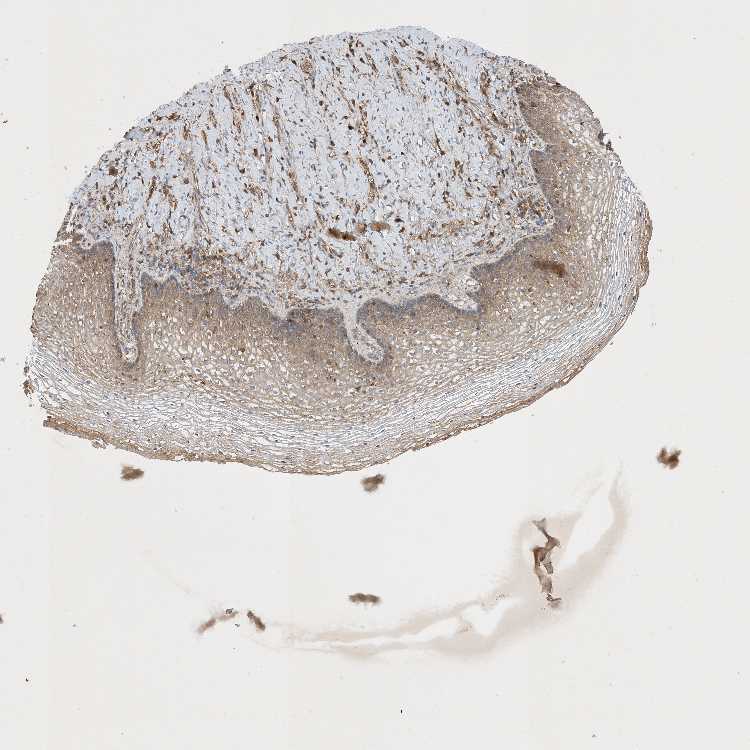

VAGINA - Antibody stainingi

Antibody staining in the annotated cell types in the current human tissue is reported as not detected, low, medium, or high, based on conventional immunohistochemistry profiling in selected tissues. This score is based on the combination of the staining intensity and fraction of stained cells.

Each image is clickable and will lead to virtual microscopy that enables deeper exploration of all samples and also displays staining intensity scores, fraction scores and subcellular localization as well as patient and tissue information for each sample.

Antibody HPA031511

Squamous epithelial cells Medium